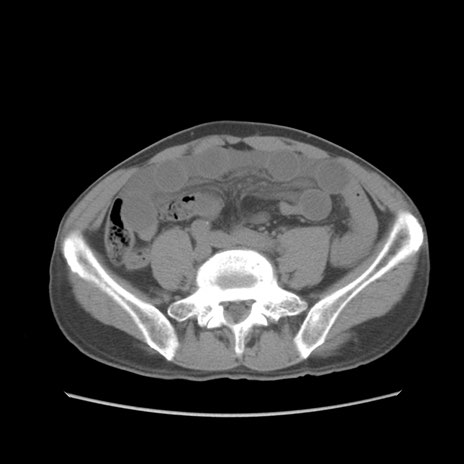

症例56 CT(横断像)

脂肪ウインドウ